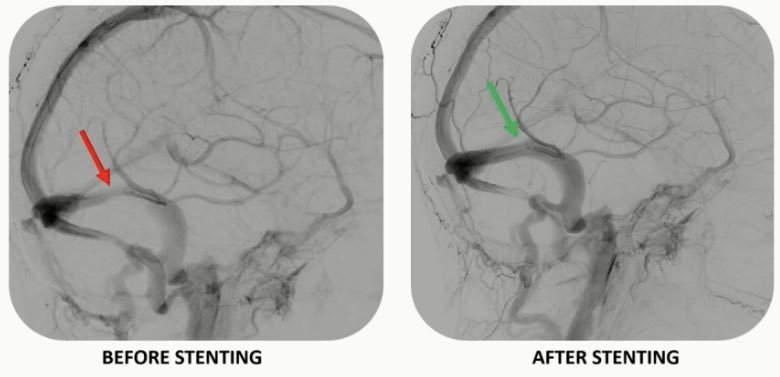

Results from the STAT trial, now published in @TheAJNR, have indicated stent-assisted #Coiling is not superior to coiling alone in unruptured intracranial #Aneurysm cases with a high risk of recurrence - as per William Boisseau, @RaymondJeanMD1 et al neuronewsinternational.com/stat-trial-ste…